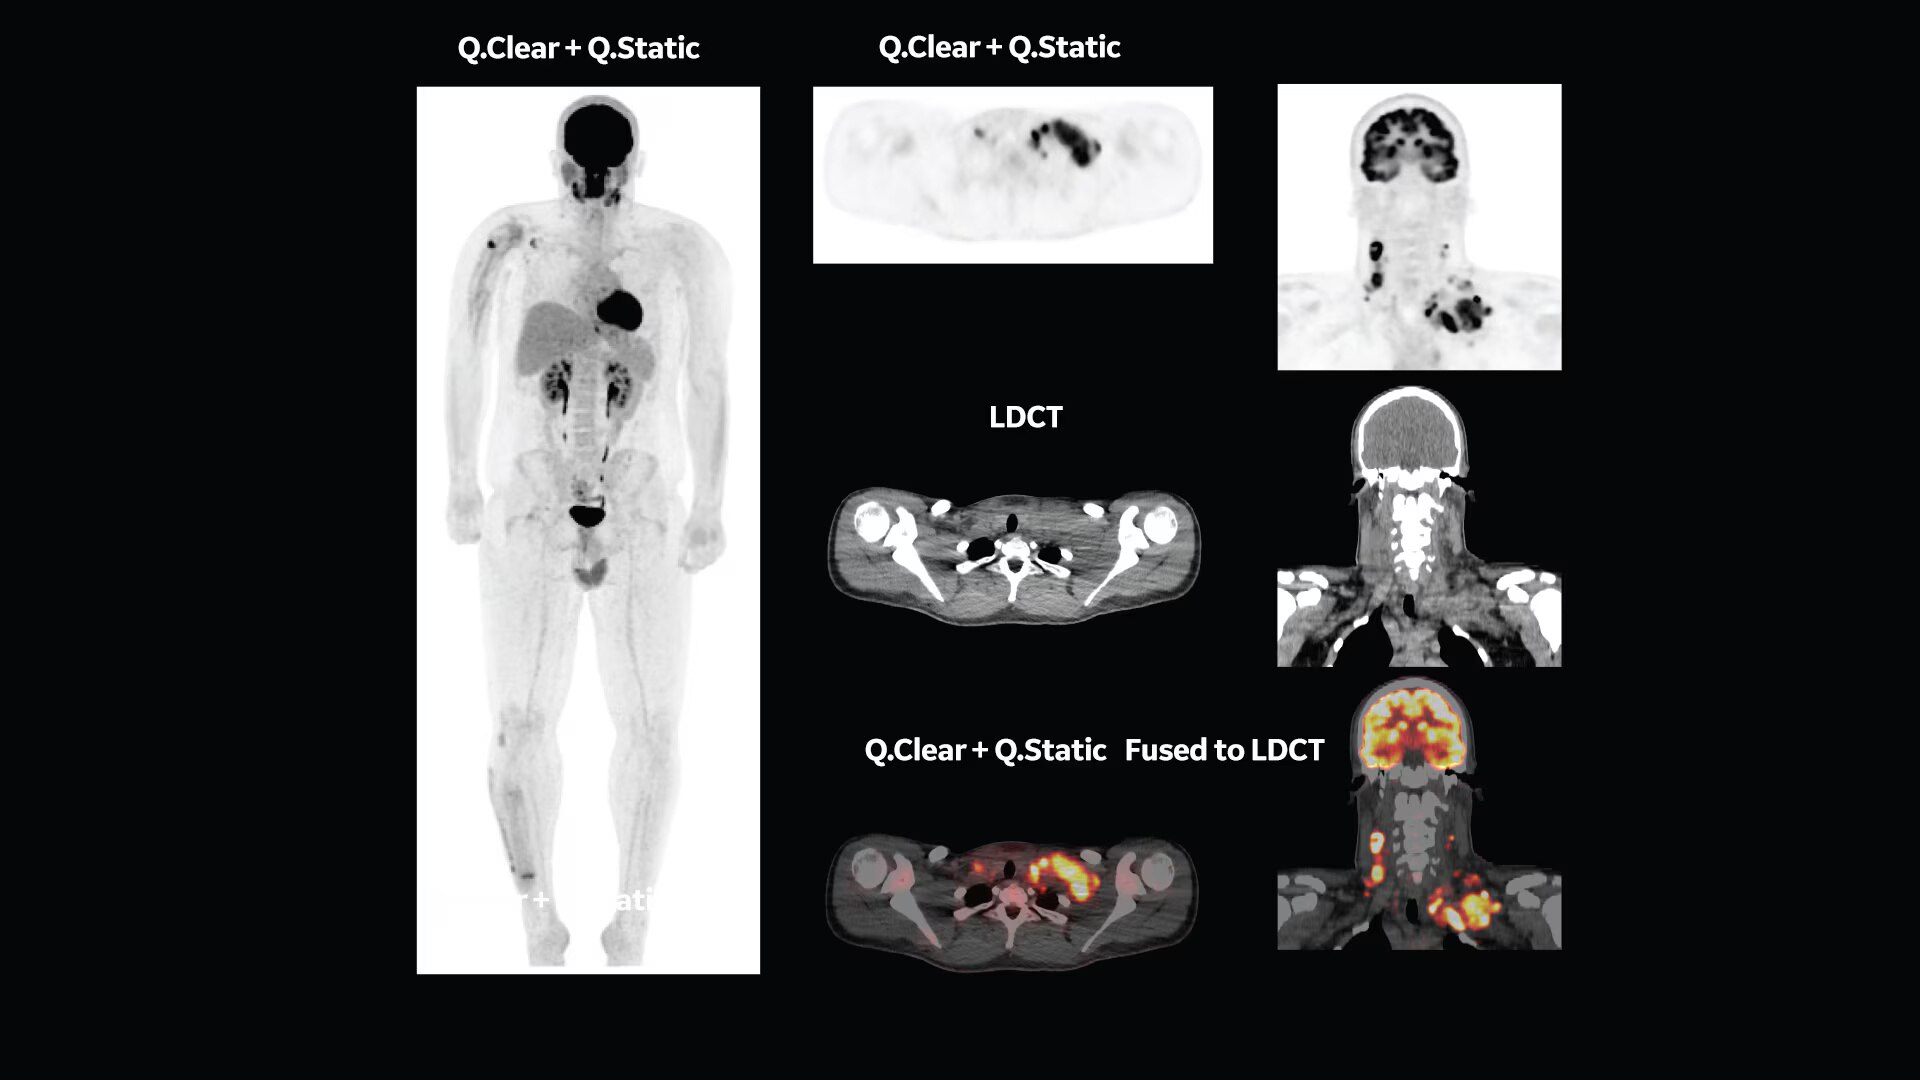

Q.Clear (BSREM): accurate data points to trusted treatment

Since its introduction, Q.Clear has delivered fast and efficient quantitation readings for confident diagnosis and precise treatment response assessment. Up to a 2x improvement in quantitative SUV (SUVmean). Up to a 2x improvement in image quality (SNR).